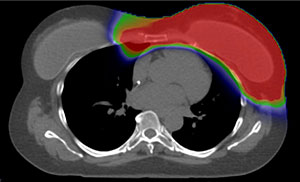

Proton Therapy

Red: High Radiation Dose |

Green: Intermediate Radiation Dose |

Blue: Low Radiation Dose